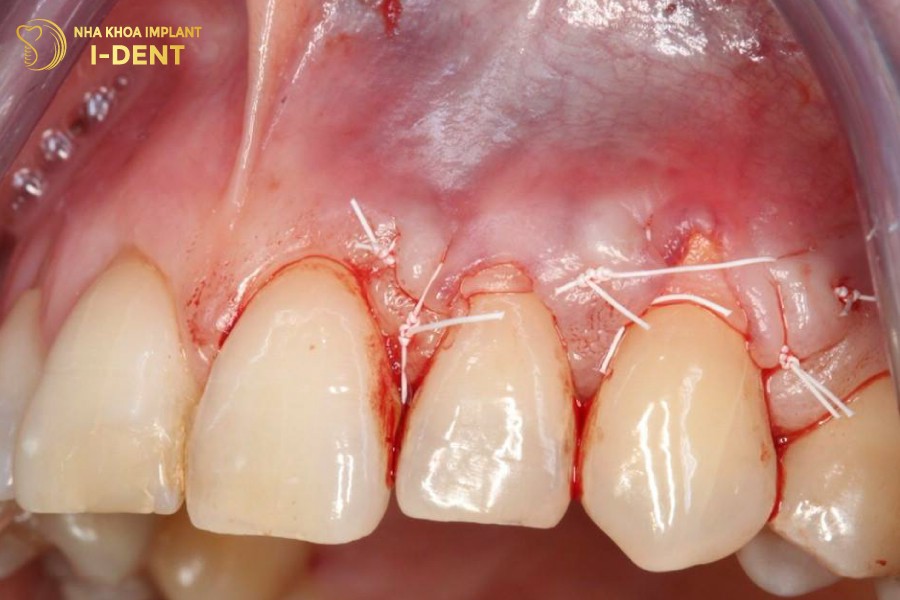

- Ghép vạt lợi được tiến hành khi phần lợi đã bị khuyết quá nhiều, không thể bao bọc chân răng được nữa. Bác sĩ sẽ sử dụng mô ghép rời tự thân, mô trong khoang miệng để cấy ghép vào phần lợi bị tụt.

Phẫu thuật ghép vạt lợi khi mô nướu bị teo đi quá nhiều